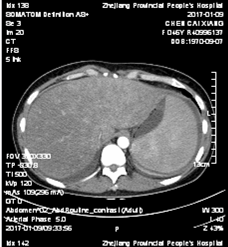

全腹增强CT:胸、腹腔积液;脂肪肝;慢性胆囊炎

表现;脾脏体积增大;肠系膜区、腹膜后、子宫旁可见多发淋巴结显示(图1)。

图1